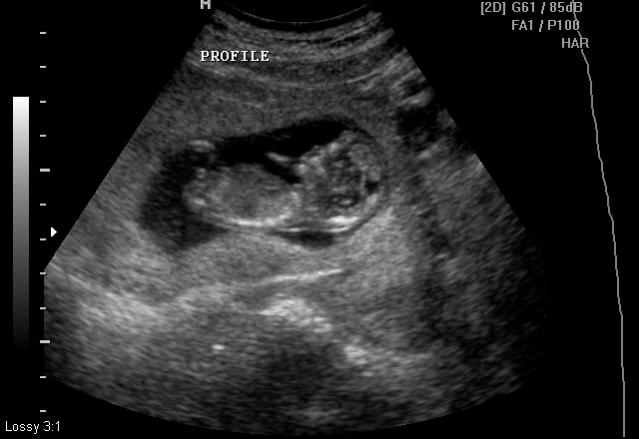

Aqua's Bubs Nub for my GenderDreaming friends

UPDATE - ITS a BOY! from the 17th week ultrasound . Thank you all.. Just feels great

Hi Folks,

I had my U/S on Friday. We did not expect the Peri to take a guess on our gender but to our surprise she did. She also did a butt shot which I thought was too early for 12.2 weeks. I request you ladies to take a look and let me know your opinion and please let me know which one among the 2 pictures is more accurate in determining. Thanks for looking.

The scratched out part on the butt shot is the perinatologist's guess.

Attachment 125Attachment 127